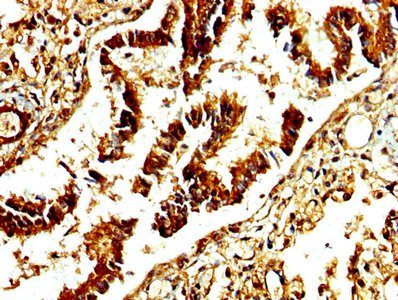

Immunohistochemistry of paraffin-embedded human heart tissue using CSB-PA001311LA01HU at dilution of 1:100

Immunohistochemistry of paraffin-embedded human liver tissue using CSB-PA001311LA01HU at dilution of 1:100

IHC image of CSB-PA001311LA01HU diluted at 1:250 and staining in paraffin-embedded human lung tissue performed on a Leica BondTM system. After dewaxing and hydration, antigen retrieval was mediated by high pressure in a citrate buffer (pH 6.0). Section was blocked with 10% normal goat serum 30min at RT. Then primary antibody (1% BSA) was incubated at 4°C overnight. The primary is detected by a biotinylated secondary antibody and visualized using an HRP conjugated SP system.